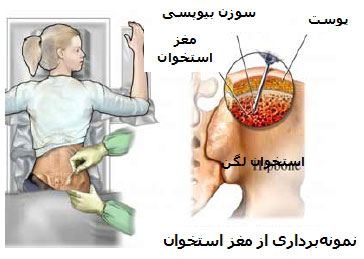

عکس سرطان استخوان. برخی از انواع اصلی سرطان استخوان عبارتند از. سرطان مغز استخوان یکی از انواع سرطان است که به دلیل اختلال در تولید گلبول ها و پلاکت های بدن به وجود می آید. رشد ناهنجار استخوان می تواند بدخیم یا خوش خیم باشد. این تصویر سرطان استخوان است که کاملا روی جمجمه قابل دیدن می باشد.

روش های عکس برداری می توانند به تعیین محل و اندازه ی تومورهای استخوان و گسترش یا عدم گسترش آن ها به سایر نقاط بدن کمک کنند. در این مقاله با علائم سرطان مغز استخوان و نیز روش های درمان آن آشنا می شوید. یک تومور رشد غیر طبیعی بافت در بدن است. سلول های توموری توانایی تنظیم کردن ندارند بنابراین سلول های بیشتری تولید می کنند و منجر به تشکیل یک توده می شوند در حالی که بسیاری از تومورها سرطانی.

تشخیص سرطان استخوان. استئوسارکوم شایع ترین نوع است که بیشتر بر کودکان و نوجوانان زیر 20 سال تأثیر می گذارد. جراحی اغلب اولین انتخاب درمانی می باشد اگرچه گاهی اوقات قطع کردن عضو لازم می باشد. درمان سرطان استخوان به نوع سرطان بستگی دارد.